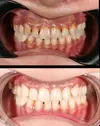

Dental Caries

Tooth Loss

Dental Crowding

Tooth and Gum Diseases